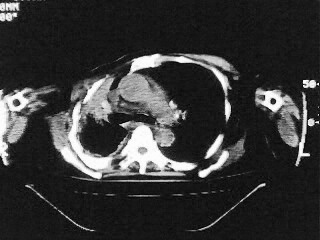

以下是引用随光逐影在2009-2-10 0:07:00的发言:[br]1)右肺放射性肺炎并节段性肺不张?请结合相关病史。2)右侧胸膜肥厚、粘连。3)心包膜增厚(或心包少量积液)。